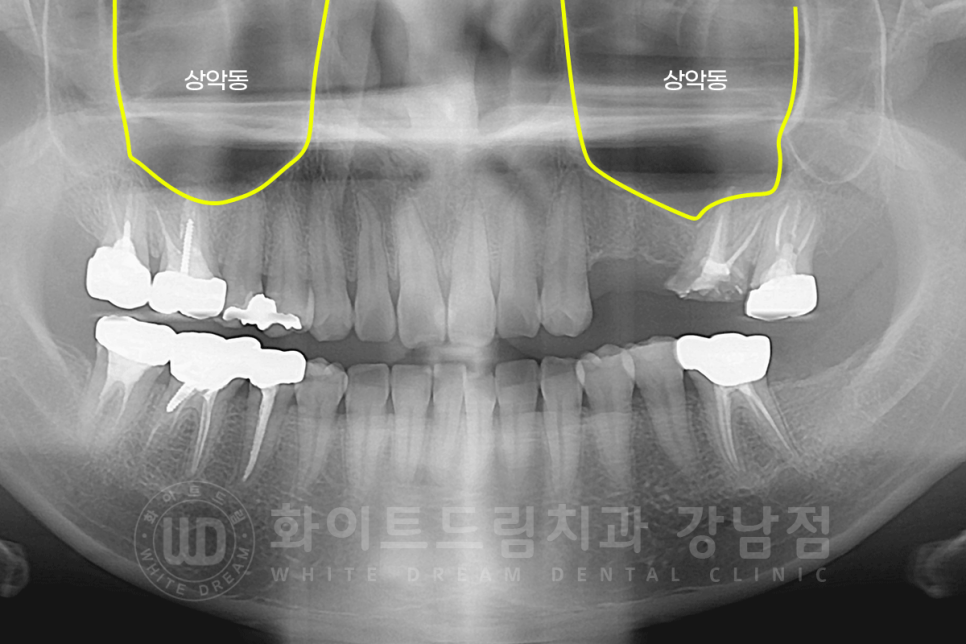

상악 어금니 부분은 상악동이라는 구조물로 인해서 대부분의 환자분들이 잇몸뼈가 얇습니다.

두꺼우신 분들도 있지만, 대부분 얇으신 상태로 있으신 분들이 더 많은데요.

원래 잇몸뼈가 다른 부위에 비해 얇은 공간인데 치아를 발치하고 임플란트를 할 정도라면

염증으로 인해 잇몸뼈가 원래 보다 더 소실된 상태이기 때문입니다.

상악동 거상술은 (sinus) 상악 어금니 부분에 진행하는 술식입니다.